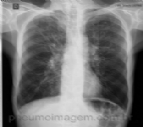

O PNEUMOIMAGEM ALCANÇA 2000 AMIGOS NO FACEBOOK

Alcançamos hoje o número de 2000 amigos no Facebook! Graças a vocês, hoje o PneumoImagem se constitui na maior comunidade em Pneumologia do Facebook no Brasil! O PneumoImagem surgiu há três anos como um site de imagens em Pneumologia, on...